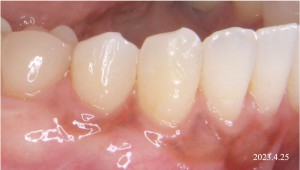

Before

右下の犬歯に歯肉退縮を認める。

※治療前の右下犬歯から小臼歯部